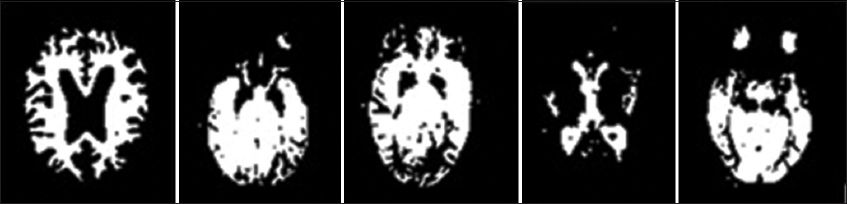

• a. Using contrast limited adaptive histogram equalization (CLAHE) which performed to enhance the contrast of specific ranges by adjusting the intensity levels according to local histograms [26], as shown in Fig. 3. This leads to additional detailed illustration of the crucial structural features of and improve our technique.

Fig. 3. The effect of applying CLAHE on the images and raising the contrast value.